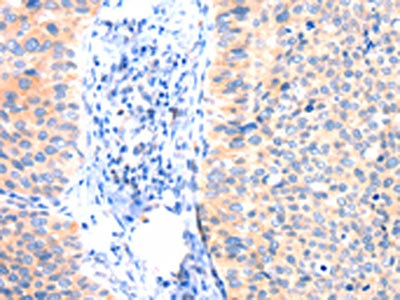

The image on the left is immunohistochemistry of paraffin-embedded Human cervical cancer tissue using CSB-PA981926(ANK3 Antibody) at dilution 1/50, on the right is treated with synthetic peptide. (Original magnification: x200)